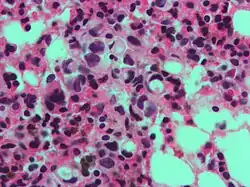

En histología, una célula en anillo de sello es aquella célula con una vacuola grande. El tipo maligno se observa predominantemente en carcinomas.

El nombre de la célula proviene su aspecto; las células en anillo de sello aparentan ser anillos de sello . Contienen una gran cantidad de mucina, la cual empuja al núcleo hacia la periferia de célula. El contenido de mucina en las células en anillo de sello imita la apariencia de un agujero para el dedo y el núcleo imita aspecto de la cara del anillo en perfil.